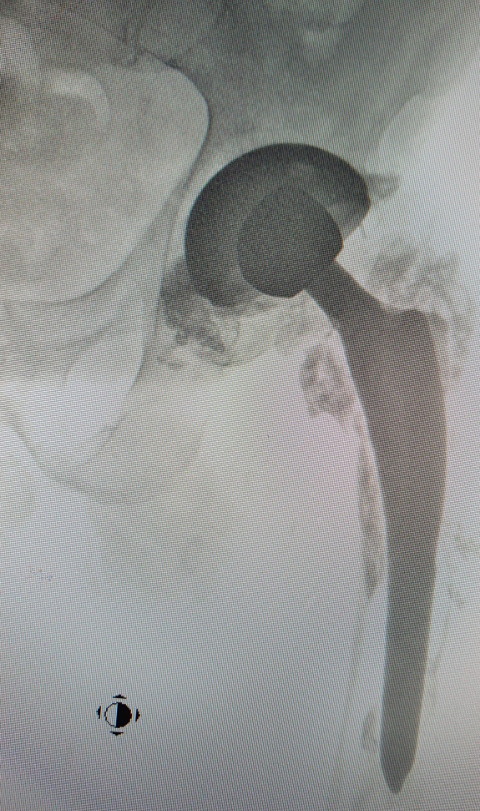

A 35-year-old man suffering from necrosis of the femoral head of the left hip joint underwent surgical treatment consisting of drilling the necrotic head and filling the femoral neck with bioceramic elements (Fig. 1). The porous bioceramic material had the following chemical composition: 97% Al2O3, 2.5% MgO, and 0.5% CaO.17 The manufactured material (open porosity, 70–80%) was characterised by external and internal pores with pore diameters between 100 and 800 μm. The outer and the inner pores were filled with healthy bone tissue adherent to the ceramic material. Bieniek17 the material was used to fill bone cysts and postsurgical or trauma-related bone defects.

Twenty-seven years later, due to the development of the secondary degenerative disease of the left hip joint, the patient underwent implantation of a total hip joint replacement in which metal/polyethene articulation was used, and ceramic fragments were carefully removed intraoperatively. In this case, a protocol of rinsing the operated joint with an electric pulsation system was used during the revision procedure, as in the case of PJI (periprosthetic infection). Six years after this procedure, the patient was observed to have deformation of the metal head of the endoprosthesis, appearing in control X-rays with relatively minor changes in the thickness of the polyethylene (acetabular insert). The head deformation was accompanied by defects that were visible in the form of radiolucencies located in the third, closer to the femur and in the area of the lower pole of the acetabulum (Fig. 2). The patient reported increasing pain in the left hip joint (increasing with weight bearing), and therefore qualified for revision surgery. The examination revealed severe macroscopic deformation of the metal head of the endoprosthesis, the formation of extensive defects in the proximal part of the femur (greater and lesser trochanter), with perforation of the femur and loosening of the stem of the primary endoprosthesis, as well as bone cysts in the periacetabular area (without destabilisation). The cavities were filled with dark content (specific to metal abrasion products), indicating severe metallosis and the metal neck of the femoral stem was severely scratched. Intense contamination of the polyethylene surface of the insert of an unknown origin was also observed (Fig. 3,4). The elements of the primary endoprosthesis removed during the procedure were subjected to further macroscopic and microscopic examination.